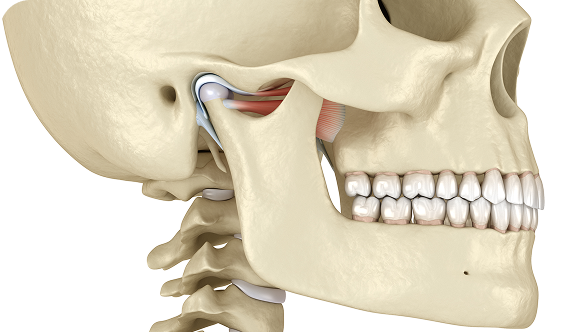

- 대한턱관절교합학회 정회원, 인정의

- 아시아 턱관절연수회 수료

- Orthognathic surgery in skeletal Class III long face with severe facial asymmetry and temporomandibular disorder(TMD) 2nd Taiwan International

Orthodontic Meeting, 2018, Poster - Changes in condylar position after 2-jaw surgery-first orthognathic surgery in a skeletal Class III patient with facial asymmetry Surgery First Summit,